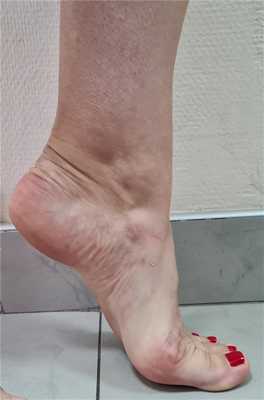

Клинический пример функционального результата у пациентки с двухсторонней болезнью Келлера 2, 2 плюсневой кости на левой стопе, и 2-3 плюсневых костей на правой стопе. Оценка амплитуды движений через 12 недель после операции.

Пациентка вернулась к занятиям в спортзале, и снова с лёгкостью выполняет выпады, приседания, отжимания. Также возобновила длительные пешие прогулки (более 10 км)

Такой хороший функциональный результат не был бы возможен без хирургического лечения и строгого соблюдения реабилитационного протокола. Пациентка была настроена на результат, каждый день занималась лечебной физкультурой, и в итоге полностью восстановила амплитуду тыльного сгибания пальцев.